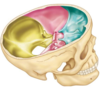

What are the main bones of the base of the skull

Go over some of the features of the skull